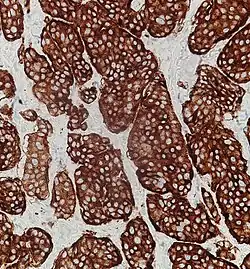

Synaptophysin immunohistochemistry of neuroendocrine tumor, staining positively

Given the diverse secretory activity of NETs there are many other potential markers, but a limited panel is usually sufficient for clinical purposes.[1] Aside from the hormones of secretory tumors, the most important markers are: